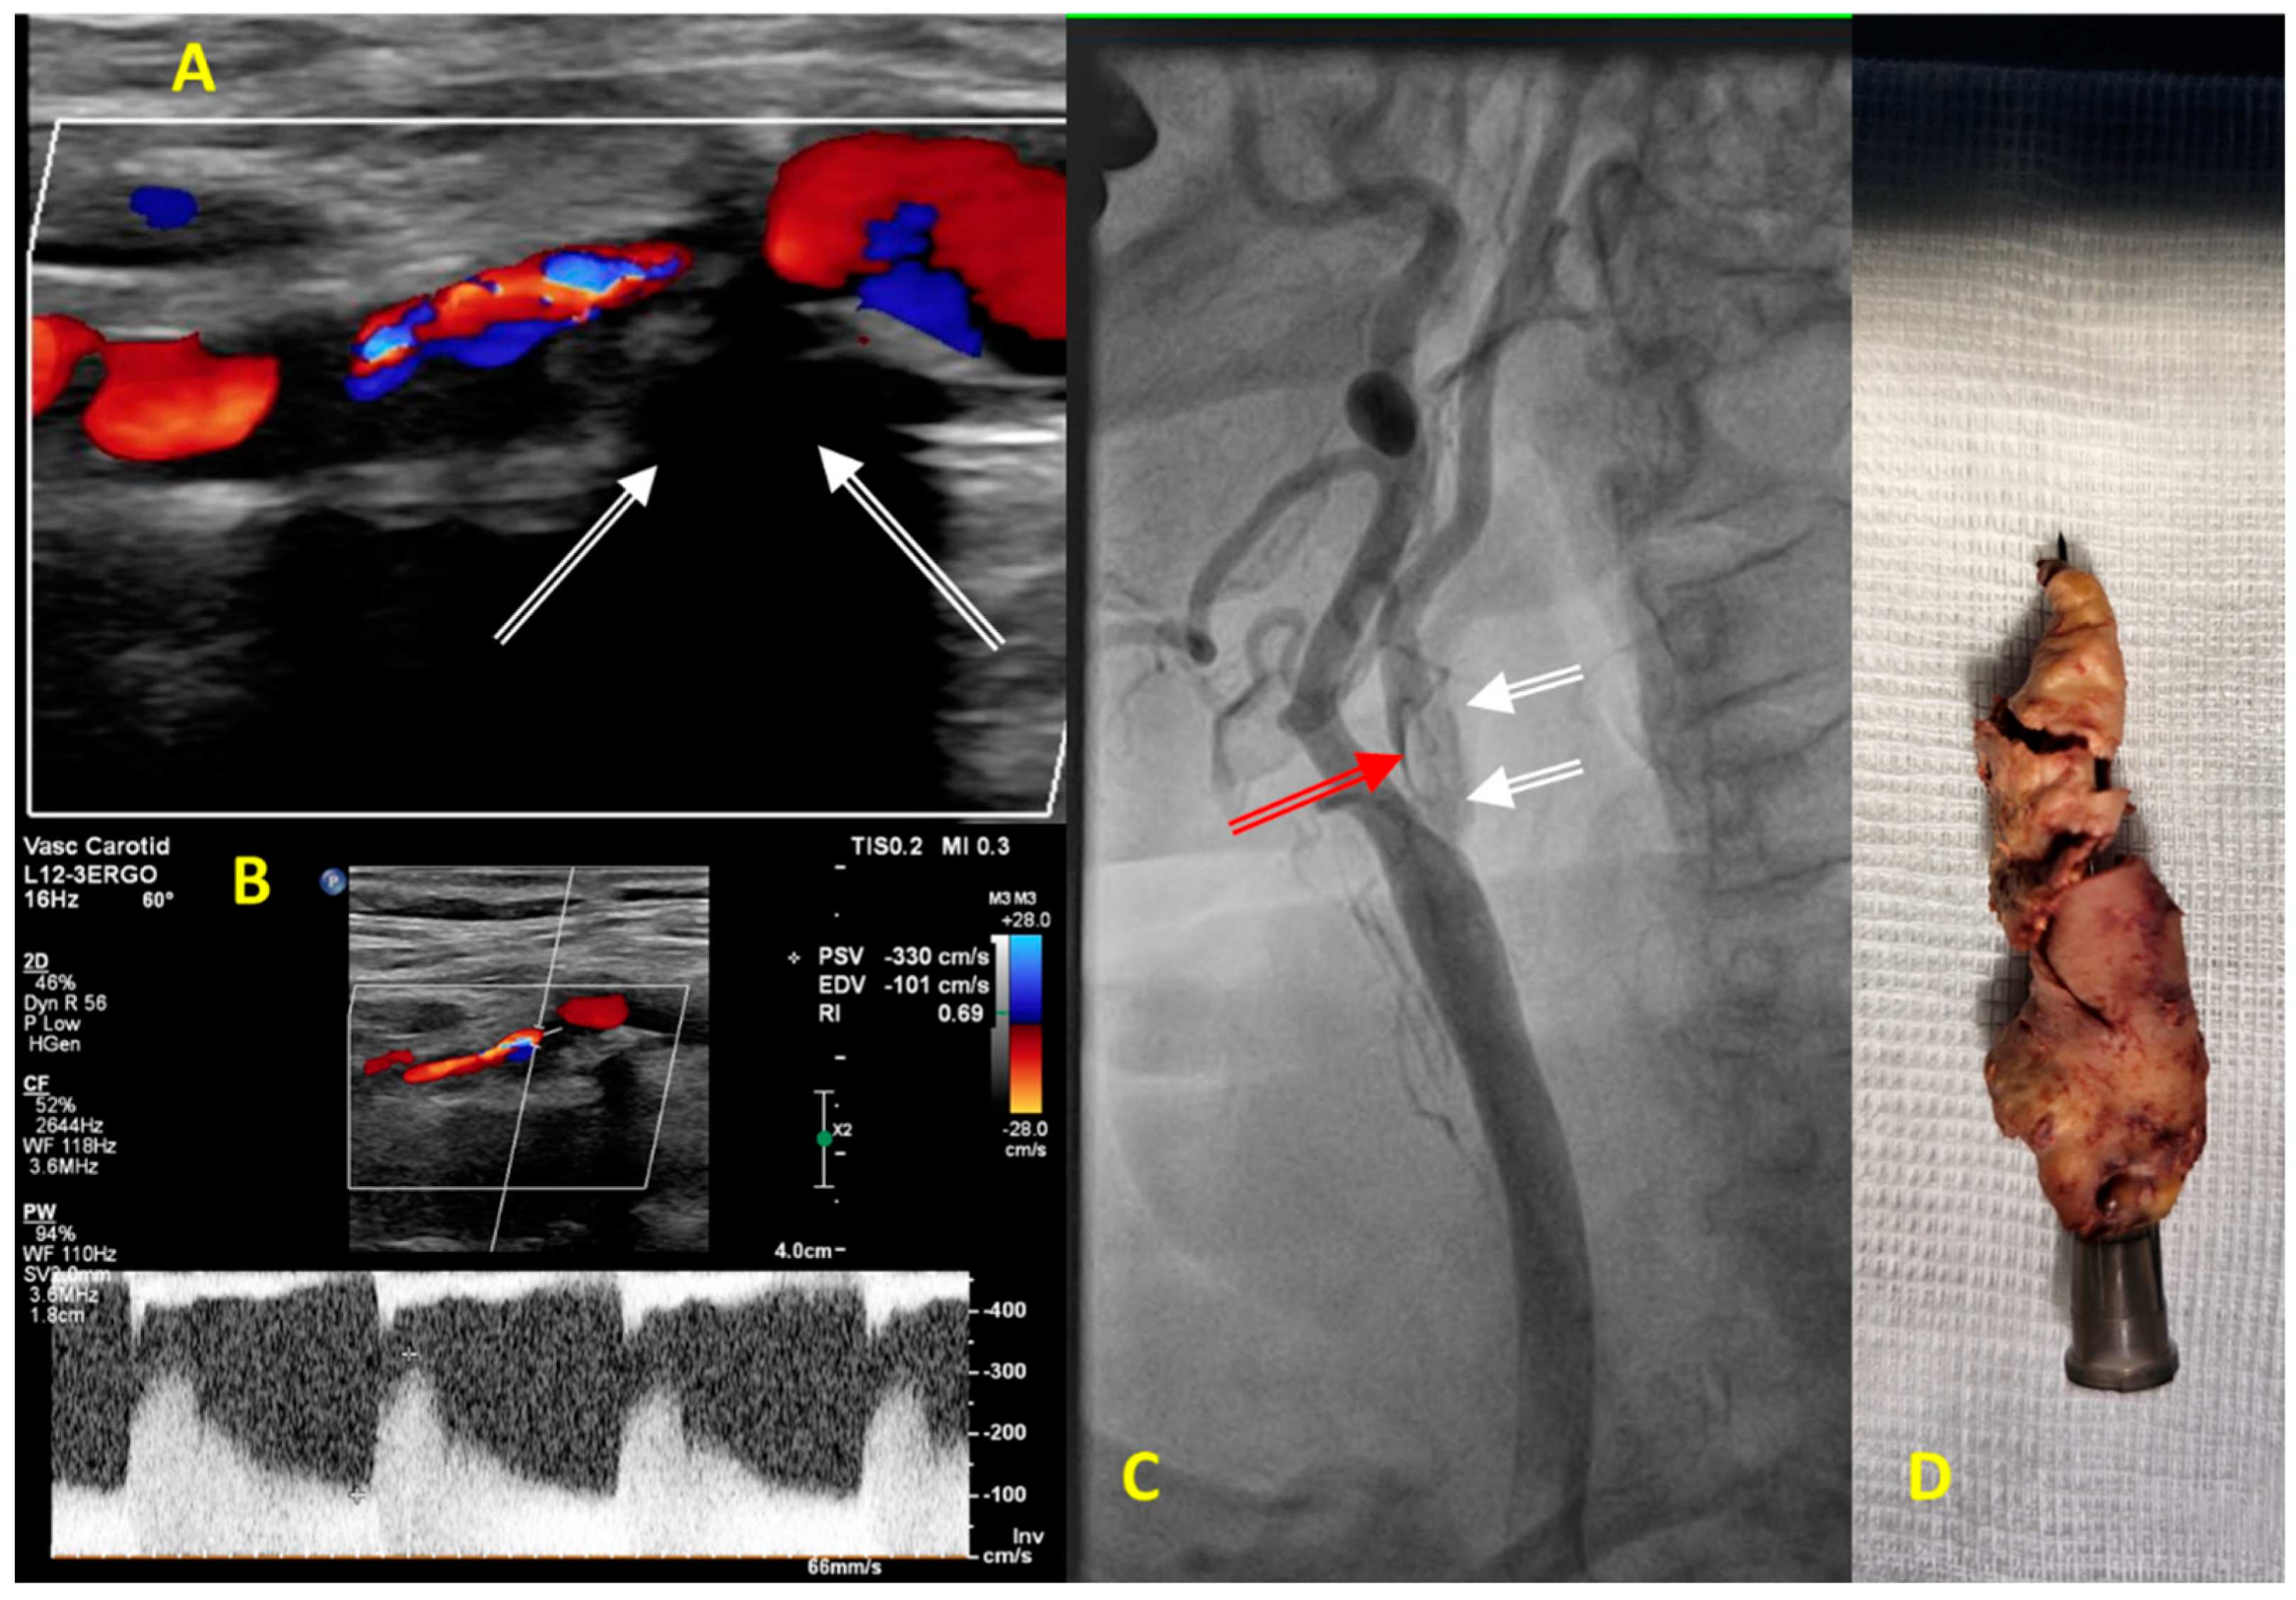

| Predominant morphology and pattern of mature atherosclerotic plaque | Large lipid and necrotic core, decreasing thickness of fibrous cap, high infiltration of inflammatory cells, neo-angiogenesis, reduction in smooth muscle cells, propensity for plaque surface ulceration and embolization. | Few lipid and necrotic elements, thick fibrous cap, sparse vasa-vasorum, many smooth muscle cells, limited accumulation of inflammatory cells. | Large lipid and necrotic core, decreasing thickness of fibrous cap, high inflammatory cell infiltration, neo-angiogenesis, reduction in smooth muscle cells, plaque rupture leading to thrombosis and vessel occlusion. | Late manifestation of atherosclerosis, atherosclerotic lesions form at a later age and are therefore ‘young’ despite the older age of the individual. Plaque morphology: infiltration of inflammatory cells, lipid and necrotic core, excessive calcification process. | |

| Diversities in the elderly patients | Severely calcified atherosclerotic lesions; stenosis in more than one carotid/vertebral artery; excessively elongated vessels, often with loop formation or acute angles <90%; high arterial stiffness and raised vascular resistance; atherosclerotic lesions in intracranial segments and cerebral arteries. | Diffuse, multilevel atherosclerotic lesions, also involving the tibiofemoral trunk and arteries below the knee; development of collateral circulation. In diabetics, superimposed lesions of diabetic angiopathy and peripheral neuropathy, hyalinization of the endothelium, ulcerations, trophic changes, reddening of the toes, and gangrene. | Stable atherosclerotic lesions, with a similar degree of progression and lumen reduction to those before age 70, but less prone to rupture and thrombosis. More fibrous components and calcification in plaques, fewer inflammatory cells and lower lipid composition, regression of necrotic and lipid core, better developed peripheral circulation. | Active atherosclerotic lesions, often coexisting with advanced atherosclerotic lesions in the coronary, carotid/vertebral arteries; abdominal aortic aneurysm and Leriche syndrome. | |

| Typical clinical manifestation in the elderly | Often | Dizziness, memory impairment, tinnitus, progressive deterioration of cognitive functions, dementia, general disability, falls and their consequences, increasing frailty syndrome, stroke from large extracranial arteries. | Asymptomatic or mild intermittent claudication, whole-leg fatigue, numbness, leg pain on palpitation, hypoesthesia. | Dyspnea, easy fatigue, palpitations, atrial and ventricular arrhythmia chronic coronary syndrome, increasing symptoms of HF, reduced exercise tolerance. | Sudden worsening of blood pressure control, increasing symptoms of HF, decreased exercise tolerance, angina complaints, escalation of ACEI/ARB doses may cause acute renal failure, progression of of renal failure. |

| Predominant mechanism of acute ischemia of the supplied organ | Often | Embolization of cerebral arteries, facilitated by the morphology and histopathological composition of the plaque and the distribution of stress shear forces resulting from the anatomy of the carotid artery bulb, 70–80%. | Decrease in blood flow, e.g., due to patient dehydration, infection, or calcification of the intimal layer. Obstruction of small peripheral arteries (favored by diabetes, dialysis). | Acute arterial occlusion due to plaque rupture and thrombus formation, 80–90%, mainly in men, often in women over the age of 60–65 years and above. | Hypertensive crisis, pulmonary oedema, acute circulatory failure. |

| Rarely | Acute arterial occlusion due to plaque rupture and thrombus formation, 10–20%. Hypoperfusion mechanism, 5–10% (older people tend to have well-developed collateral cerebral circulation). | Non-atherosclerotic acute limb ischemia (e.g., cardiogenic embolism—thrombus, myxoma). Plaque rupture and thrombus (usually well-developed collateral circulation protects against acute lower limb ischemia). | Microvascular embolism—ulcerated plaques rich in proteoglycans, 10–20%, common etiology in women before the age of 60–65 years. | Acute renal ischemia—generally renal failure progresses slowly in a chronic manner—it is estimated that in about 20% of chronic dialysis patients, the cause is renal artery stenosis/obstruction. | |

| Methods of diagnosing atherosclerotic lesions in older people | Preferred | Doppler-duplex ultrasound—good resolution, no need for a contrast agent. Limitation—calcifications causing an acoustic shadow make it difficult to assess the vessel lumen. CT and MRI of the brain—diagnosis of ischemic lesions. | Doppler-duplex ultrasound—good resolution, no need for a contrast agent. Limitation—calcifications giving an acoustic shadow make it difficult to assess the vessel lumen. ABI indicates lower limb atherosclerosis when it is <0.9, but it is often nondiagnostic in people with diabetes due to intimal calcifications (ABI > 1.4). TBI in patients with diabetes and non-diagnostic ABI (>1.4); TBI < 0.7 is diagnostic for PAD. Pulse oximetry—measurement of blood pressure on the toe—a prognostic indicator of ulcer healing. | Treadmill test—assessment of exercise tolerance and detection of new ischemic changes. Echocardiography—assessment of left ventricular systolic function; wall motion abnormalities; diastolic function; exclusion of intracardiac problems such as thrombus, valve disease, pericardial effusion, features of pulmonary embolism. SPECT—assessment of viability and ischemic area on isotope. | Doppler-duplex ultrasound—good resolution, no need for a contrast agent. Limitation—obesity makes the examination difficult/impossible. |

| Limited | CTA—anatomical assessment, but test affects renal and thyroid function, caution if renal failure with eGFR below 50 mL/min/kg, calcifications make assessment of vascular stenosis difficult. MRA—anatomical assessment, possible assessment of plaque morphology, but long examination, requires administration of gadolinium (caution if eGFR < 30 mL/min); claustrophobia. | CTA—anatomical assessment, but test affects renal and thyroid function; caution if renal failure with eGFR below 50 mL/min/kg, calcifications make assessment of vascular stenosis difficult. MRA—anatomical assessment; possible assessment of plaque morphology, but long examination, requires administration of gadolinium (caution if eGFR < 30 mL/min); claustrophobia. | CTA—anatomical assessment, but test affects renal and thyroid function; caution if renal failure with eGFR below 50 mL/min/kg; calcifications make assessment of vascular stenosis difficult. MRA—anatomical assessment; possible assessment of plaque morphology, but long examination, requires administration of gadolinium (caution if eGFR < 30 mL/min); claustrophobia. | CTA offers anatomical assessment, but it affects renal and thyroid function; caution if renal failure with eGFR below 50 mL/min/kg; calcifications make assessment of vascular stenosis difficult. MRA—anatomical assessment; possible assessment of plaque morphology, but long examination, requires administration of gadolinium (caution if eGFR < 30 mL/min); claustrophobia. Scintigraphy with captopril test—not recommended for diagnosis of RAS (class III recommendation). Renal vein renin activity assessment—not recommended (class III recommendations). | |